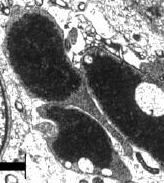

Zaadcellen ontstaan uit stamcellen en moeten dan nog rijpen. In die fase zet de zaadcel allerlei genen aan of uit. Dat heet 'imprinting'. Gaat dat fout, dan stijgt in de volgende generatie de kans op ziekten als suikerziekte en vetzucht. Een nog niet-uitgerijpte zaadcel heet een spermatide. Hiernaast zie je een spermatide in een gezond varken.

Bij de clenbuterolvarkens waren er in de spermatiden echter afwijkingen ontstaan. De spermatide hiernaast, gevonden in een varken dat clenbuterol had gekregen, heeft bijvoorbeeld twee celkernen.